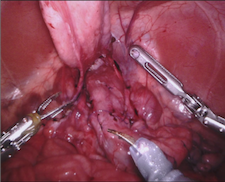

As robotic minimally invasive surgery has developed, with platforms such as da Vinci becoming the de-facto standard-of-care for certain urological, gynecological and general surgical procedures, there has been an increase in focus in how assistive systems based on computer vision and machine learning can improve surgeon performance and patient outcomes. Many potential applications are dependent on scene understanding and for this, accurate segmentation of instruments is an important component. For instance, instrument tracking algorithms which underlie automation and guidance assistance often build upon segmentation [4] or alternatively masking augmented reality overlays of 3D imaging modalities requires pixel labelling of the instruments to prevent their occlusion (see Fig. 1).

In 2017 we organized a follow-up challenge222https://endovissub2017-roboticinstrumentsegmentation.grand-challenge.org where a team at Intuitive Surgical manually segmented images from porcine robot assisted nephrectomy procedures. We aimed to improve on the previous challenge by first increasing the label quality by using hand-created labels rather than automatic labelling, secondly by adding greater variance in the background by using 10 separate procedures and finally by providing more type and part labels for the instruments.

Our dataset was made up of 10 sequences of abdominal porcine procedures recorded using da Vinci Xi systems. From each procedure we selected active sequences where significant instrument motion and visibility was observed and sampled 300 frames at a rate of 1 Hz. In cases where instrument motion ceased for several frames we manually removed these frames and extended the sequence so that exactly 300 frames remained. We provided left and right eye images from the stereo camera on the Xi system and also provided camera calibration information in case participants wished to use stereo reconstruction as a feature.

We provided the first 225 frames of 8 sequences as training data and kept the last 75 frames of those 8 sequences as test data. 2 of the full 300 frame sequences were kept as test sequences. Test labels were kept hidden from the participants. Our datasets contain 7 different robotic surgical instruments. The Large Needle Driver, Prograsp Forceps, Monopolar Curved Scissors, Cadiere Forceps, Bipolar Forceps, Vessel Sealer and additionally a drop-in ultrasound probe, which is typically held in the jaws of the Prograsp Forceps instrument. Samples from the training datasets are depicted in Fig. 2 and examples of the different instrument types are shown in Figure 3 and 4.